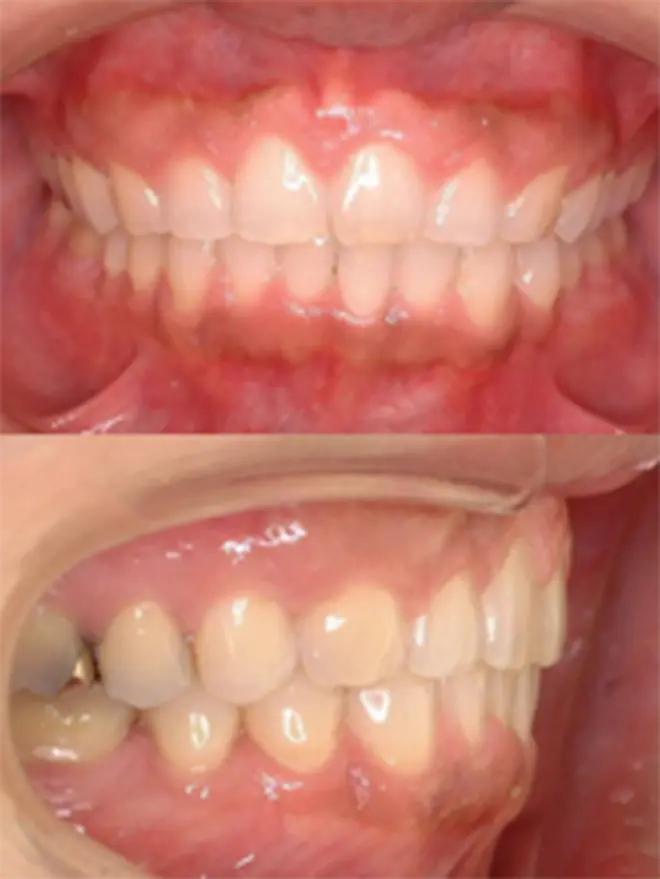

| 患者さまの年齢・性別 | 30代・男性 |

|---|---|

| 治療期間 | 2年2ヵ月 |

| 治療費(税込) | 1,567,500円 |

| 主訴 | ガミースマイルが気になる。 |

| 診断名・主な症状 | 過蓋咬合 |

| 治療に用いた主な装置 | 舌側矯正装置、歯科矯正用アンカースクリュー |

| 治療内容 |

歯科矯正用アンカースクリューにより上顎前歯を上方と後方に移動させ、ガミースマイルと上顎前突の改善を行ないました。 |

| 抜歯部位 | 非抜歯 |